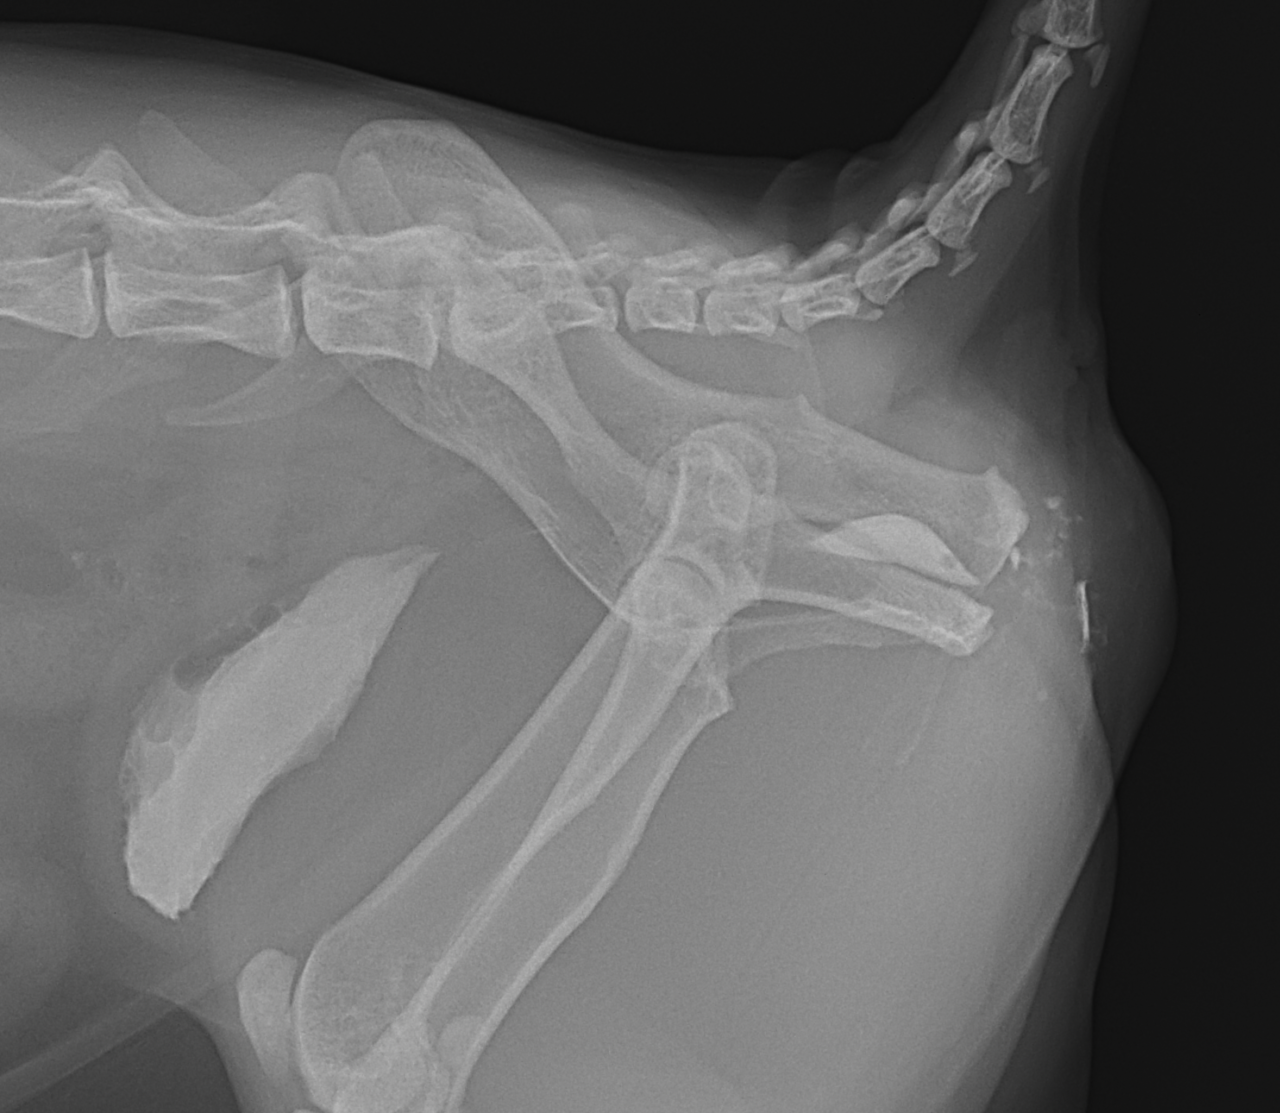

過去にかかりつけ医で会陰尿道瘻設置術を実施した猫ちゃんが、再び排尿が困難となって来たとのことで来院されました。かかりつけ医よりセカンドオピニオンがありました。尿道造影を行うと皮膚と尿道フィステルを形成した部位で狭窄と皮下に尿が漏れが生じているようです。恥骨部分に骨切り術を行い骨盤腔より尿道を誘導し、皮膚と再縫合を実施しました。会陰尿道瘻設置術の術後の合併症の一つと考えられております。